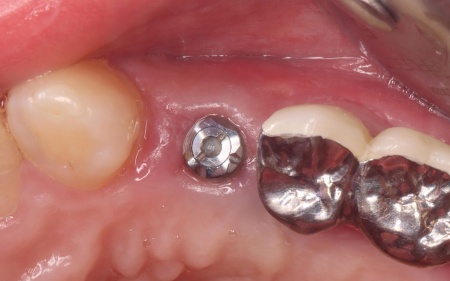

続いてインプラント手術を実施し、インプラントを正しい位置と角度で顎の骨に埋め込みました。

インプラント手術後は経過観察を行い、インプラントが顎の骨に結合したことを確認したら、インプラント上部に取り付ける人工歯を作製するために精密な型取りを実施します。

後日、完成した人工歯をインプラントに装着し、使用感や見た目に問題がないことを確認して、治療を終了しました。